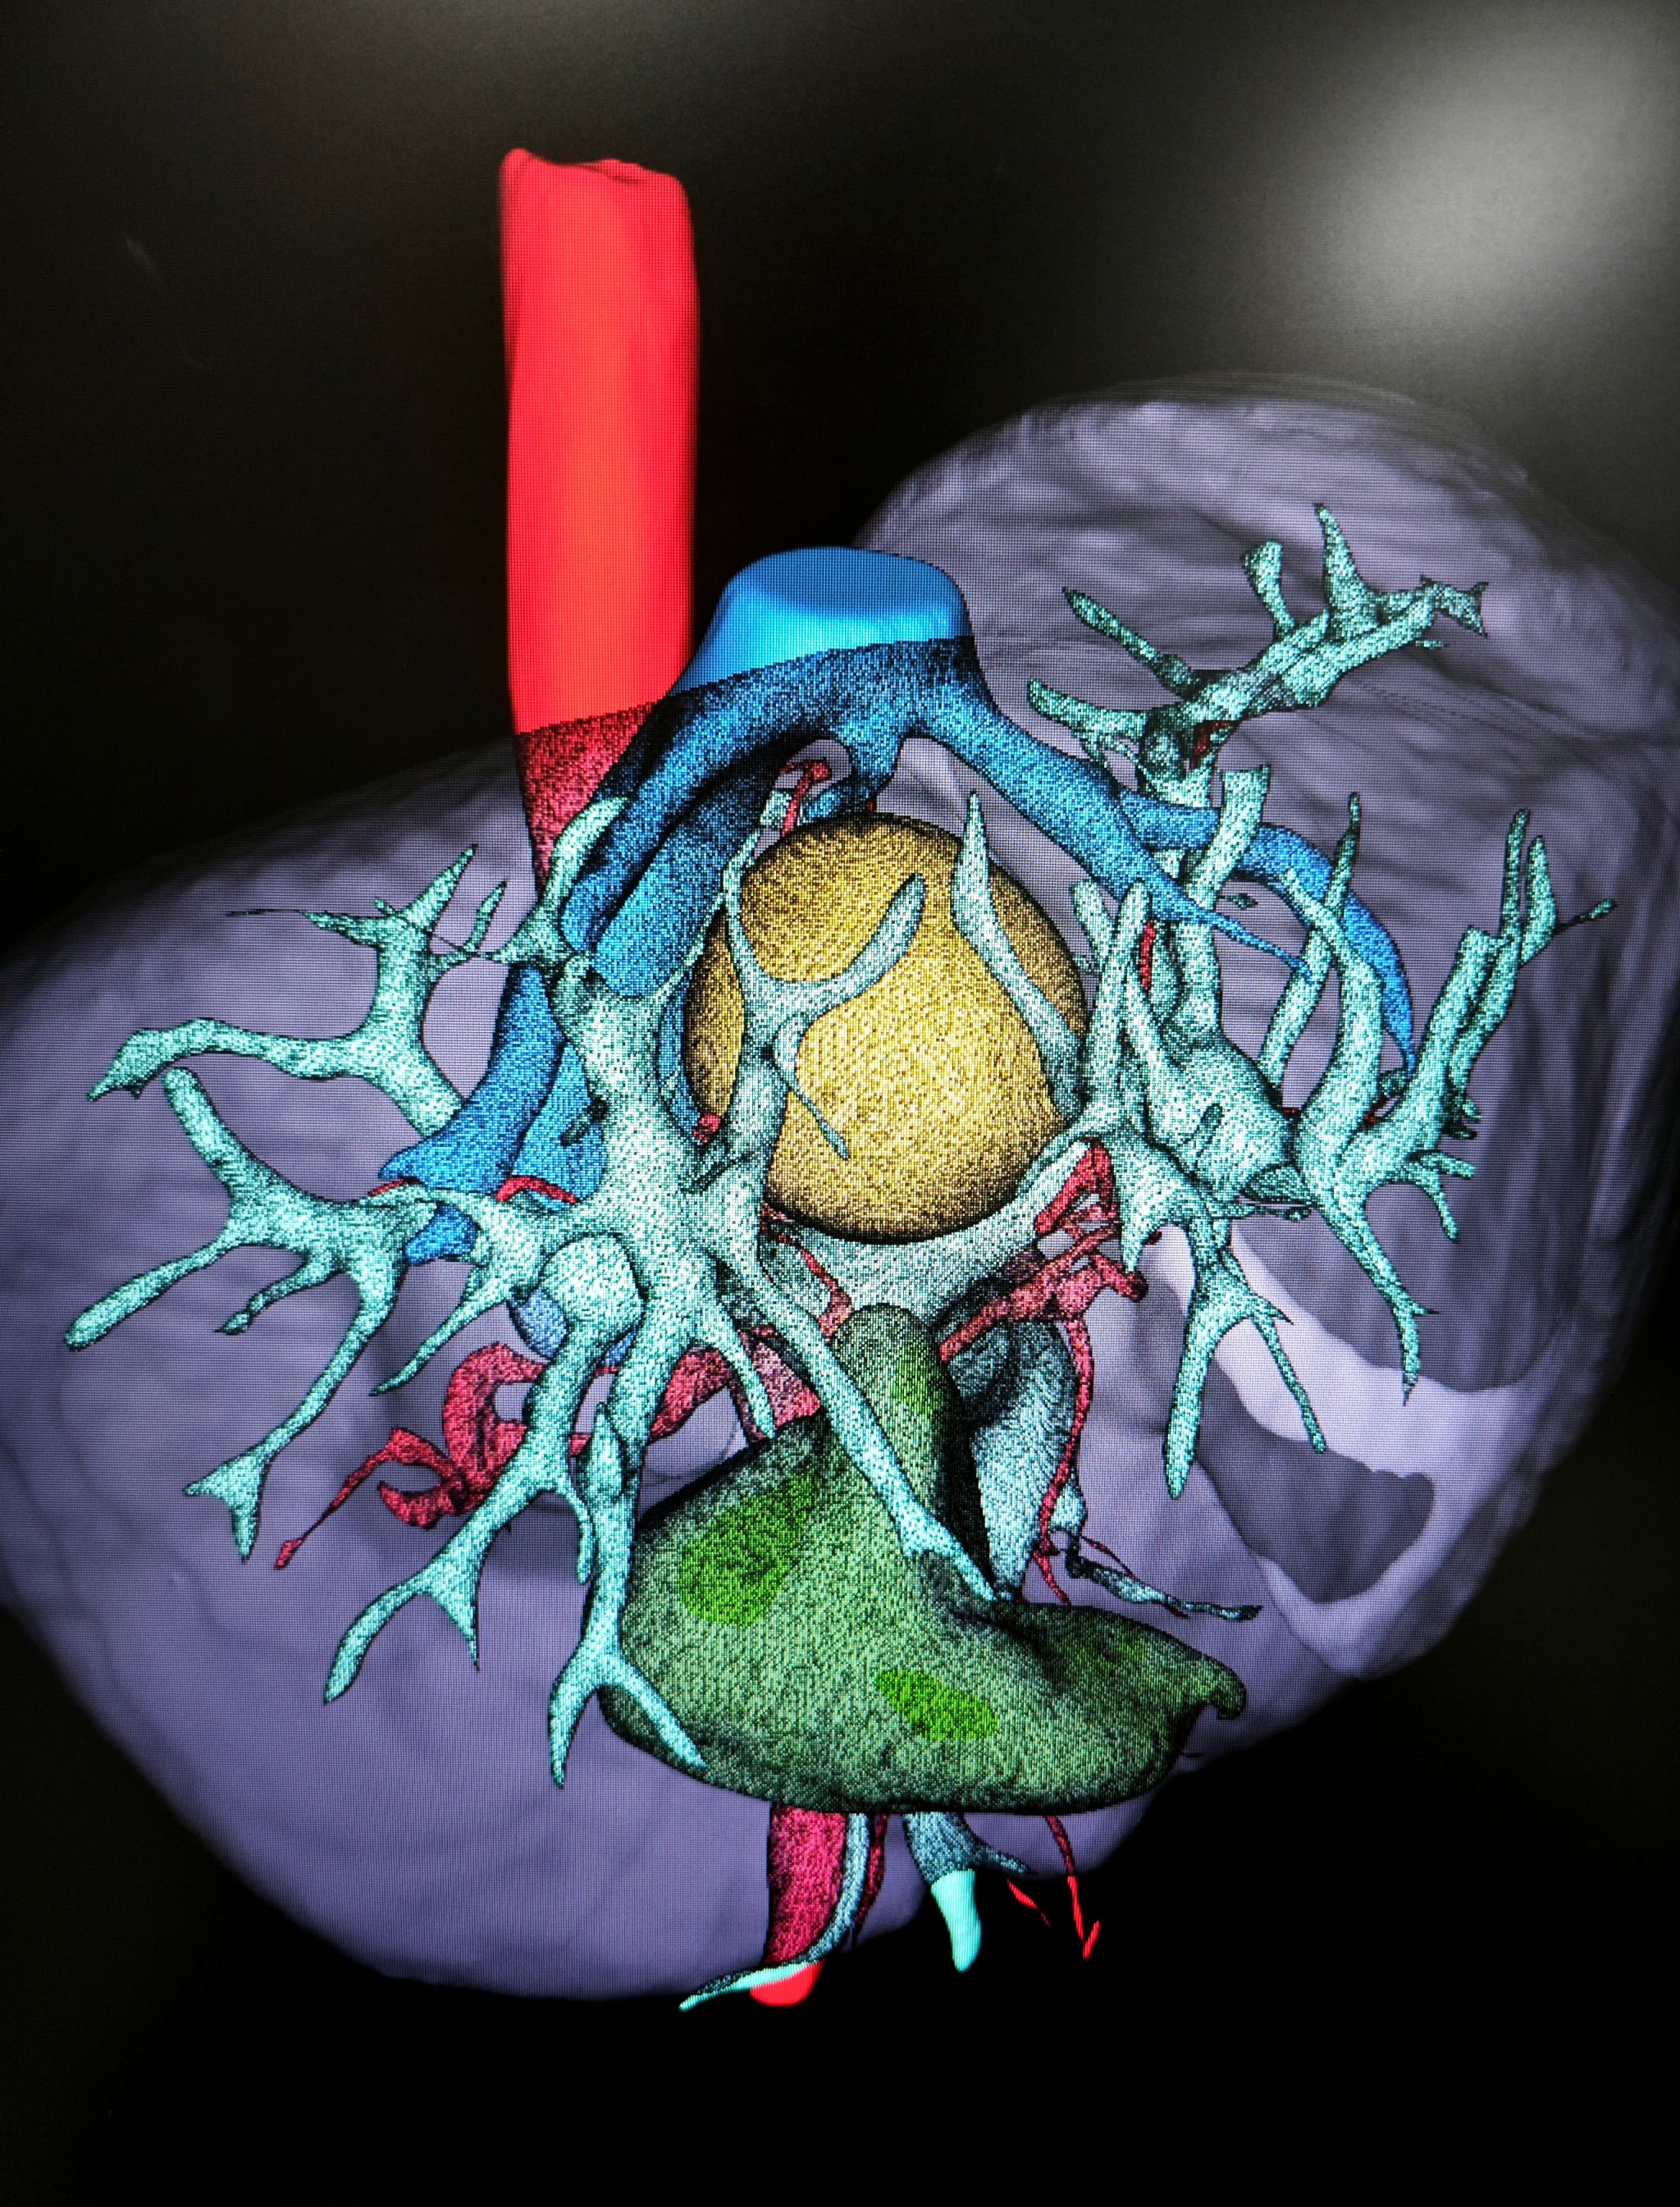

“必须把手术创伤降到最低!”团队达成共识。老年心血管内科率先行动,针对患者极高危高血压定制围术期血压管理方案;麻醉科吕建瑞教授团队设计了个体化血流动力学监测与保护策略;肝胆胰与肝移植外科王喆医师则借助三维肝脏重建技术,将肿瘤与血管的立体关系转化为“数字沙盘”。

屏幕上,血管的走向、肿瘤的边界清晰可辨。“肿瘤像一颗嵌在血管网中的‘定时炸弹’。”蒋安教授比喻道。肝胆胰及肝移植外科蒋安教授、曲凯教授、张威教授讨论后决定采用腹腔镜正中入路,劈开肝脏局部切除肿物,最大程度保留肝组织——如同在血管缝隙中“雕刻”肿瘤,既要完整切除病灶,又要保全肝中静脉、门静脉左右支及下腔静脉的完整性。

“没想到微创手术恢复这么快!”白先生感慨。特别值得一提的是,团队在术前特意用三维模型向他们讲解手术方案,“那些血管和肿瘤的立体图像,让我们真正理解了医生的良苦用心。”

4.人文温度:三维重建技术不仅用于手术规划,更成为医患沟通的桥梁,让医疗更具温度。